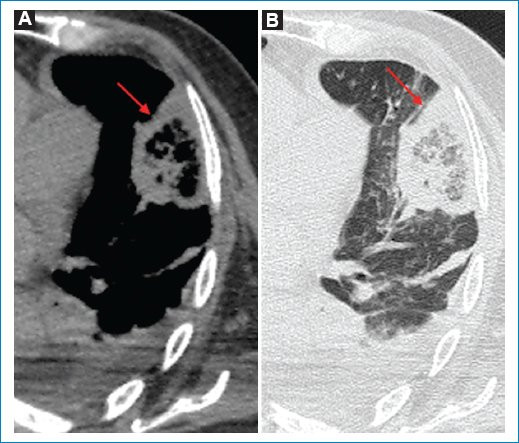

- Opacidad en cuña: presenta una especificidad del 60% y una sensibilidad del 52%5. Se trata de uno de los signos más característicos de IP, se describe como una opacidad de base pleural ancha y vértice dirigido hacia el hilio pulmonar de forma triangular, ubicada a lo largo de la superficie de la pleura visceral (costal, diafragmática, mediastínica o interlobular)3. La asociación de dicha opacidad con EP fue descrita por primera vez por Hampton en 1940 y es conocido como “joroba de Hamptom”, donde encontraron que dicha morfología en cuña era más probable en las consolidaciones observadas en pacientes con EP que en pacientes sin EP7. Como ya hemos mencionado, la ubicación periférica se debe a la afección de las ramas subsegmentarias de la arteria pulmonar, que además explicaría el dolor pleurítico y el frote pleural característicos de este cuadro clínico (Fig. 2).

Si bien la forma de cuña es la forma clásicamente descrita relacionada con IP, se ha encontrado en los últimos años que también puede adoptar morfología redondeada o de bordes irregulares, siempre manteniendo su ubicación periférica (Fig. 3)6.